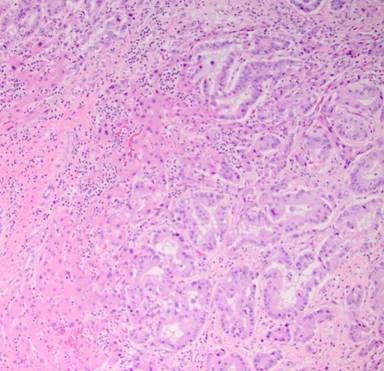

Secondary to her disease being potentially resectable, a diagnostic laparoscopy was performed to rule out extrahepatic disease. Biopsy of the segment 6 liver lesion demonstrated infiltrating glands staining diffusely for CK7, CK19, and CK20 consistent with a gallbladder primary (Figures 3 and 4). Concern was raised about the size of the left hemi-liver and the patient underwent portal vein embolization.

Figure 3. Histology of original gallbladder primary demonstrating well-to-moderately differentiated papillary gallbladder adenocarcinoma with invasion into lamina propria. |

The pathology specimen demonstrated a 10.0x6.5x0.5 cm papillary, pink, circumferential tumor located primarily in the body and neck of the gallbladder. Additional papillary areas that were non-contiguous with the main tumor were also identified in the body and fundus. The final cystic duct and liver margins were negative for any evidence of malignancy. Adenocarcinoma present in the liver resection specimen was morphologically identical to the gallbladder primary tumor (Figures 5 and 6). There was evidence of lympho-vascular invasion; however, no lymph nodes were identified in the sizable portal node dissection specimen. The patient underwent adjuvant chemotherapy with cisplatin and gemcitabine for six months and was followed by her local medical oncologist with tumor markers and serial imaging. Two years after her initial diagnosis, PET-CT showed a new 25x17 mm hypodense mass in the pancreatic head involving the main pancreatic duct causing mild upstream duct dilation and pancreatic parenchymal atrophy (Figure 7). There was no evidence of vascular invasion or biliary dilation on CT imaging. Endoscopic ultrasound showed a round hypoechoic mass in the inferior aspect of the pancreatic head and uncinate process measuring 23x21 mm in maximal cross section diameter. A fine needle aspirate (FNA) of the pancreas head mass demonstrated metastatic gallbladder carcinoma consistent with patient’s gallbladder primary.

Figure 5. Histology of metastatic papillary adenocarcinoma to the liver identical to gallbladder primary. |

Histologically, our patient was found to have a diffuse, well-to-moderately differentiated papillary adenocarcinoma with tumor invasion into lamina propria (T1a). In general, PGAs presents at an earlier stage with up to 64% of patients having localized disease [3]. Sporadic reports also show that noninvasive PGA has a markedly improved survival compared to its invasive counterpart. The 5-year survival rate for PGA can be as high as 41% compared to 8-10% for patients with other types of gallbladder cancer [3]. Albores-Saavedra et al. examined the clinical and morphologic features of 16 noninvasive papillary carcinomas of the gallbladder and compared their clinical behavior with that of invasive papillary carcinomas. Noninvasive criteria included the following: predominant (>80%) papillary architecture, lack of infiltration into the wall of the gallbladder, and tumor size greater than 1.0 cm. The 10-year relative survival rate for tumors confined to the wall of the gallbladder was 52% compared to a 10-year survival of less than 10% in patients with lymph node metastases. Moreover, invasive papillary carcinomas of the gallbladder had a significantly better prognosis than invasive non-papillary carcinomas, which has a 10-year survival of only 30% when confined to the gallbladder wall [6].